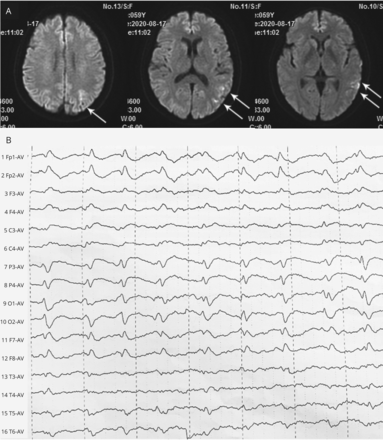

59岁的女人面对亚急性发作的手笨拙失忆紧随其后。她伸手报道困难对象,虽然她可以看到他们。考试(视频1)显示视神经共济失调,或者20/30的视力,完整的视野,和正常的finger-to-nose测试。Hyperintense diffusion-weighted MRI信号在左temporo-parieto-occipital皮层,周期性三相的复合物在脑电图(图),高架t-tau CSF建议Heidenhain变异克雅氏病的疾病。1病人接受支持性护理,发展到无着丝粒的缄默症。视神经视觉引导的手臂动作ataxia-inaccuracy visuomotor障碍与涉及后顶叶皮层的损伤有关。2

图

Diffusion-Weighted MRI和脑电图

(一)Diffusion-weighted MRI显示hyperintense信号(箭头)在左temporo-parieto-occipital皮层。(B)脑电图显示周期在1 / s三相的复合物。